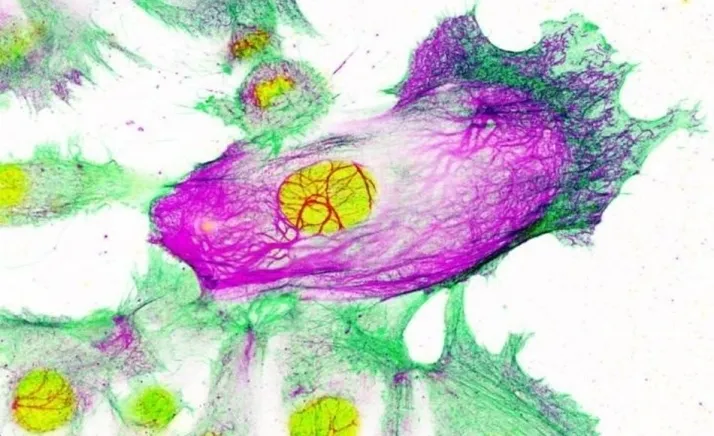

Este hallazgo, que se acaba de publicar en la revista 'Nature Communications', han descubierto que la enzima FASN, cuyos niveles se encuentran elevados en numerosos tipos de cáncer, es crucial para que se produzca uno de los procesos esenciales por el cual una célula normal se transforma en cancerosa. Bloquear FASN en un modelo animal de cáncer de mama agresivo retrasó la aparición de tumores y amplió su supervivencia en un 68 por ciento.

El equipo ha trabajado para desarrollar este proyecto con el Hospital de Fuenlabrada, Quirón de Pozuelo y el Hospital de la Princesa. En esta investigación se ha podido demostrar que cuando las células no tienen FASN, un complejo de proteínas implicadas en la síntesis de ácidos grasos, no son capaces de realizar uno de los pasos más importantes para que se formen tumores: normalmente las células de los tejidos sanos crecen en capas, bidimensionales, y cuando se amontonan suelen morir. La capacidad de amontonarse y crecer en aglomerados es una de las características de los tumores.

El grupo del doctor Quintela ha comprobado que las células sin FASN no son capaces de dar este paso fundamental en el desarrollo del cáncer. No solo eso, sino que modelos animales en los que se elimina FASN no llegan a desarrollar tumores. El bloqueo de este mecanismo ha retrasado la aparición de tumores y ampliado la supervivencia un 68 por ciento. Aunque la interrupción de la función de FASN no elimina tumores ya establecidos, estos datos tienen muchísima importancia en el campo de la prevención del cáncer de mama, abriendo una vía nunca explorada hasta el momento.